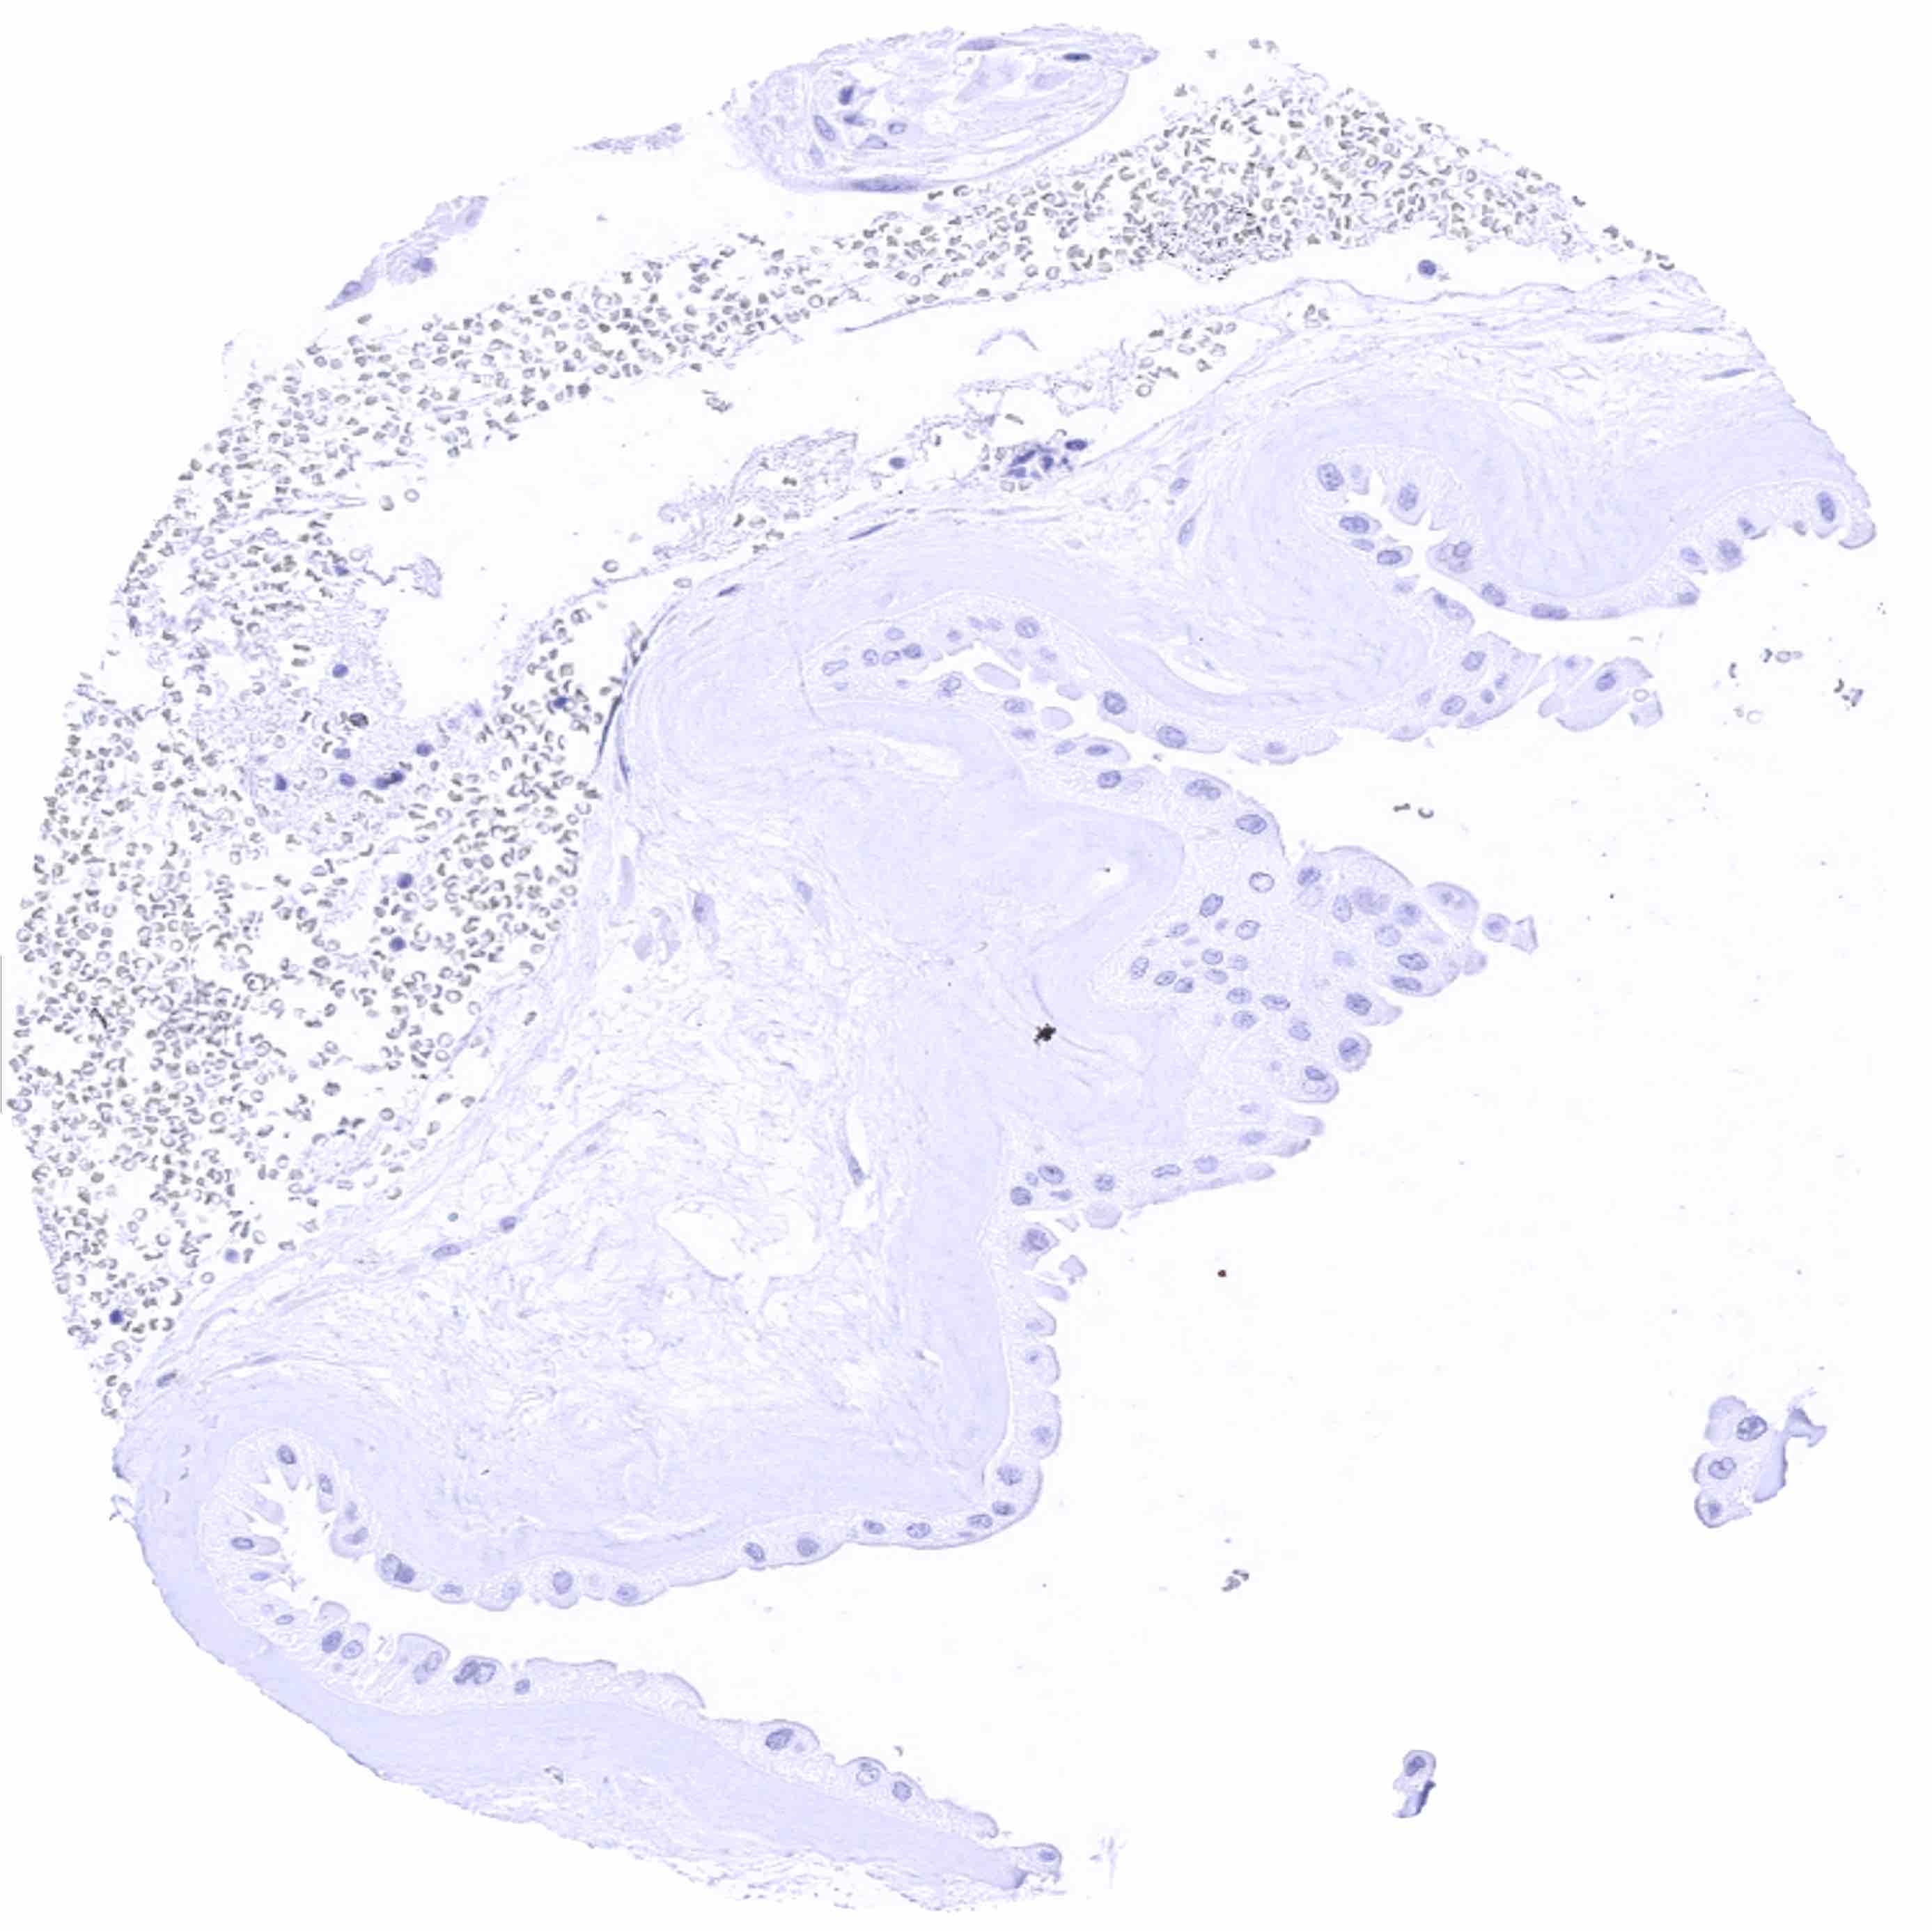

Uterus, endocervix